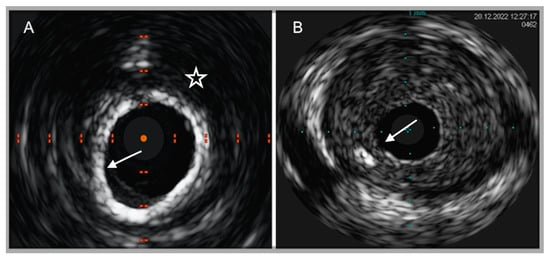

4.1. Intravascular Ultrasound

4.2. Optical Coherence Tomography